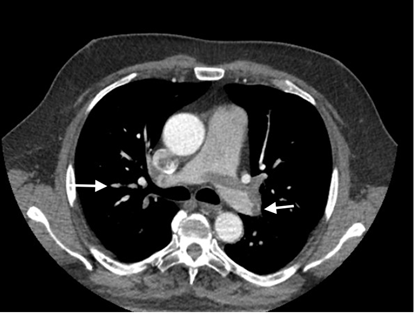

The Computed tomography (CT) pulmoangiography demonstrated a massive thrombus at the pulmonary trunk bifurcation with extension to the right lung arteries, which were almost completely blocked (Figure 2). Considering unstable hemodynamics and massive mobile thrombus in the right chambers, we proceeded with surgical thrombectomy.

Figure 2 Computed tomography showing proximal pulmonary emboli in the right pulmonary branch (white arrows).

A 76-year-old male with prior systemic hypertension, obesity class III, COPD, and NIDDM presented to the emergency department with acute complaints of worsening dyspnea with cyanosis, tachyarrhythmia - 160 b/min, hypotension - 80 / 60mmHg, D-dimer value -1800 ng/ml. He had undergone an endoscopic cholecystectomy a week before. CT pulmoangiography demonstrated dilated pulmonary trunk with a saddle pulmonary embolism, extending into the left and right pulmonary arteries as in the distal branches (Figure 3). Hemodynamic instability and recent cholecystectomy led us to decide on emergency surgical embolectomy.

Figure 3 CT pulmoangiography - saddle pulmonary thrombosis, proximal and distal pulmonary emboli (white arrows).